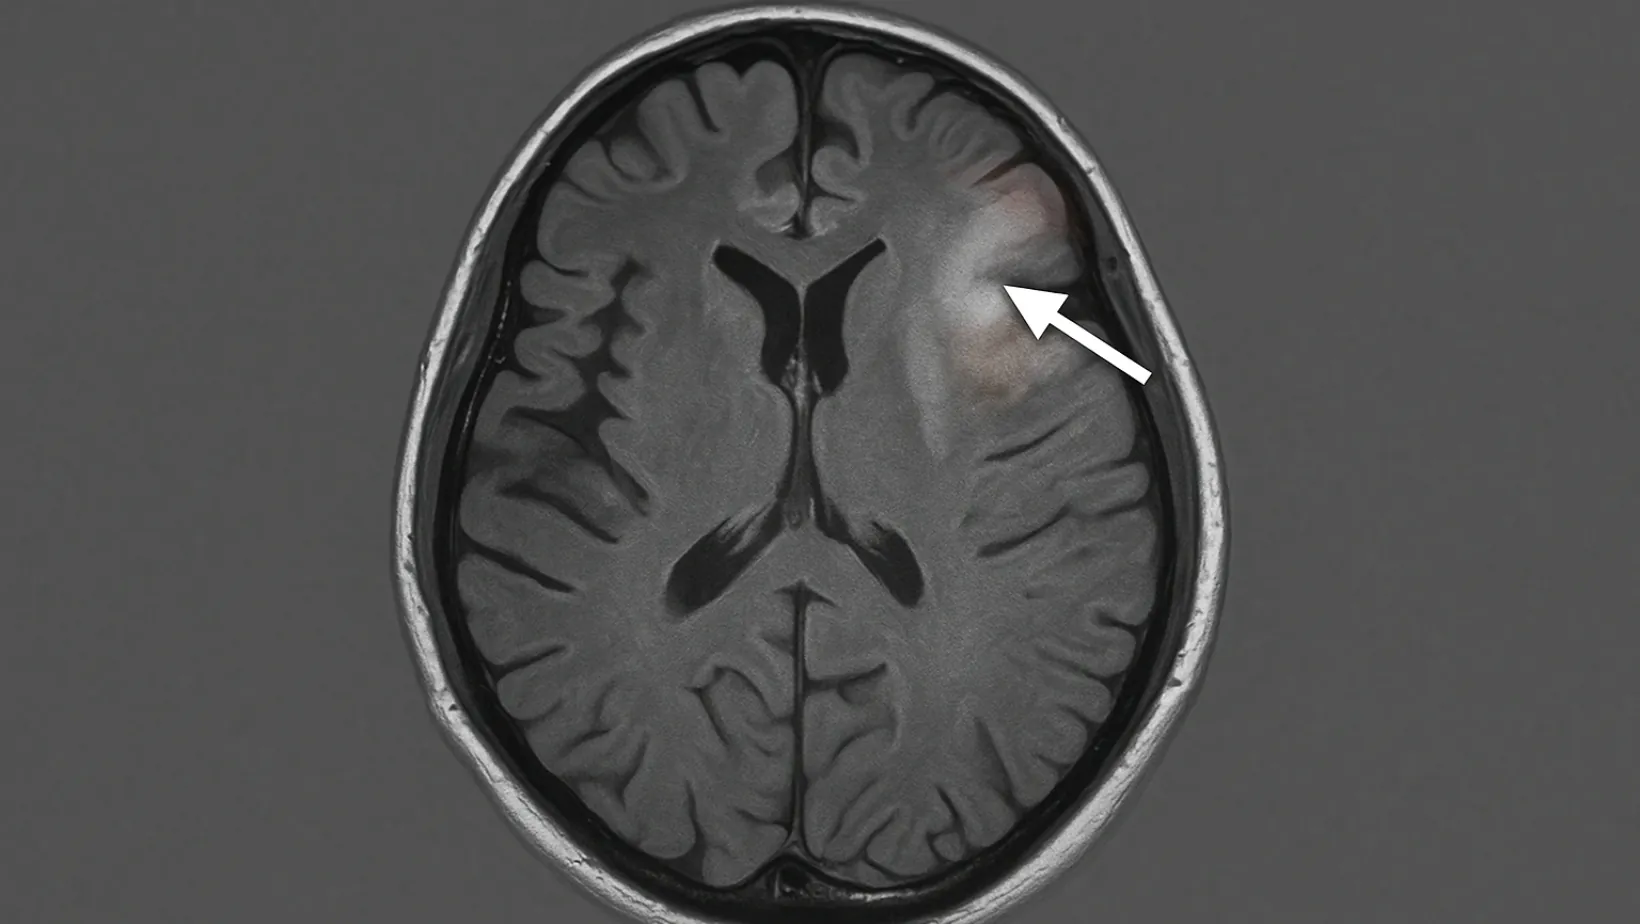

Brain Lesions: Causes, Symptoms, Treatments

Brain lesions are areas of damage in the brain tissue, and understanding them…